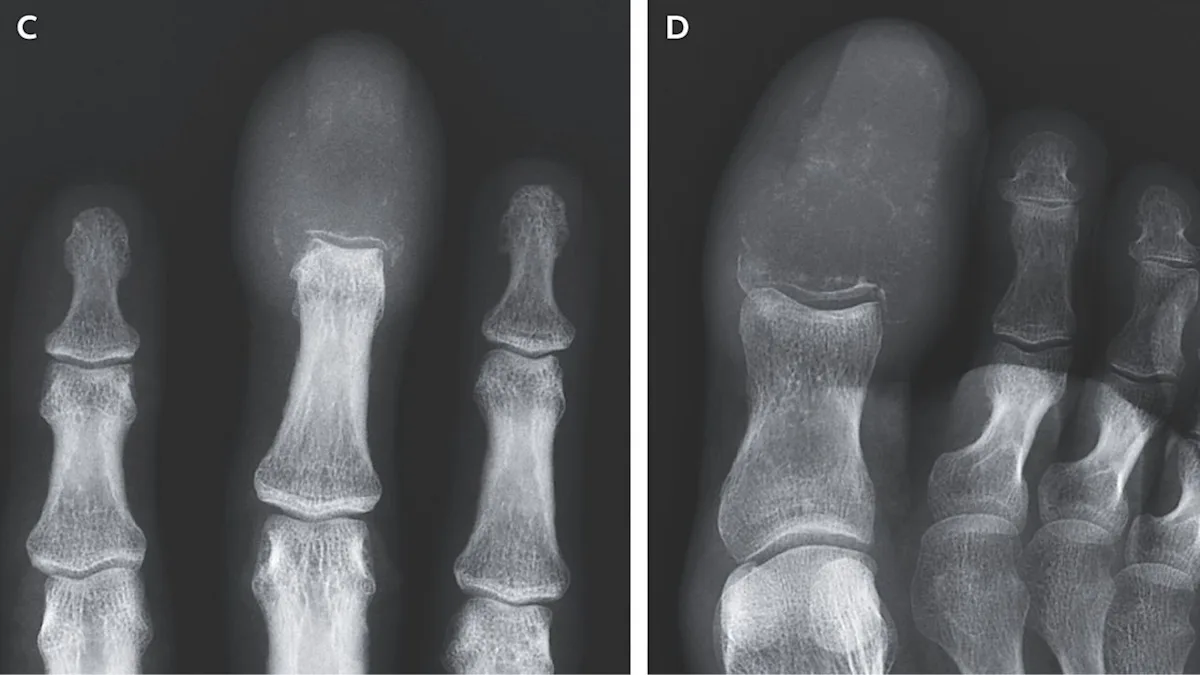

A 55-year-old man with advanced lung cancer developed rare acrometastasis, causing swelling and destruction of finger and toe bones, which is often a late sign of widespread cancer and associated with poor prognosis. The case highlights the importance of recognizing unusual symptoms as potential indicators of metastatic disease.